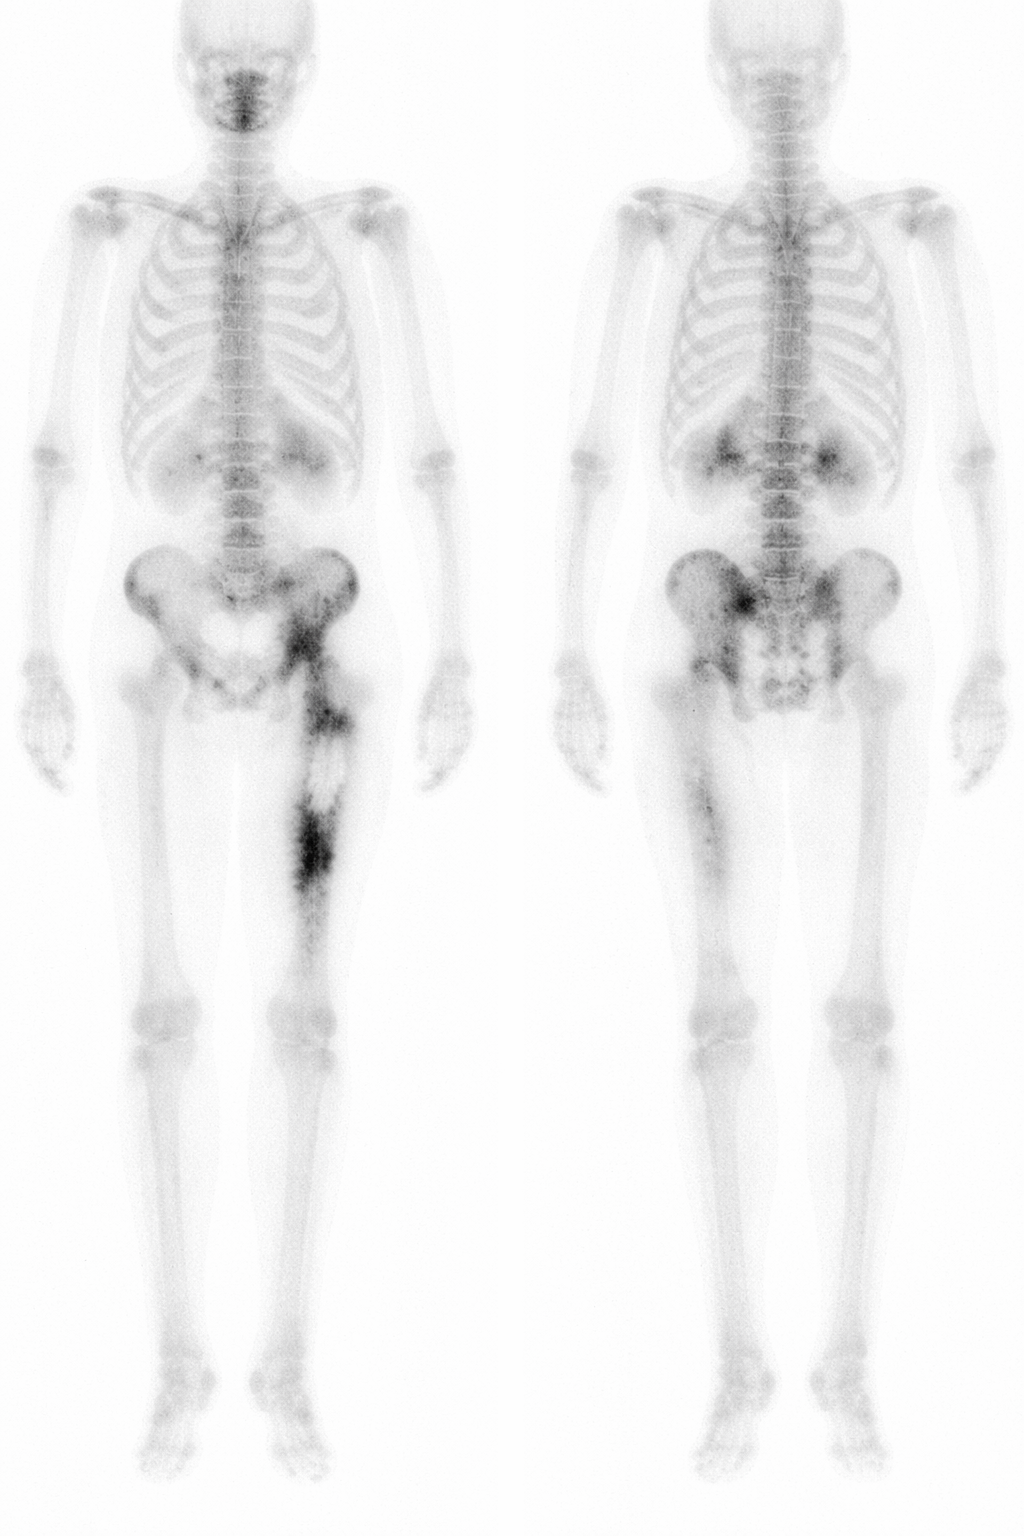

Gammagrafía ósea en tumores

La gammagrafía ósea (habitualmente con 99mTc-fosfonatos) es una prueba de medicina nuclear que refleja, sobre todo, el recambio óseo y la actividad osteoblástica. En oncología músculo-esquelética sigue siendo útil para responder preguntas concretas, aunque en muchos centros ha cedido protagonismo frente a técnicas más modernas (PET/TC y RM de cuerpo entero) cuando se busca una estadificación más completa o una valoración más precisa de respuesta.

La gammagrafía ósea no “ve” el tumor como tal: detecta cómo reacciona el hueso. El radiotrazador se fija en zonas donde suele existir mayor perfusión local y, sobre todo, mayor actividad de remodelado óseo. Por eso es una técnica muy sensible para detectar lesiones “activas”, pero no permite por sí sola diferenciar con fiabilidad una metástasis de una fractura, una artrosis, una infección o un tumor primario.

La gammagrafía sigue siendo especialmente útil cuando interesa una visión global del esqueleto, por ejemplo ante la sospecha de multifocalidad ósea o cuando no se dispone de PET/TC o RM de cuerpo entero.

- Gammagrafía planar de cuerpo entero tras administración de 99mTc-fosfonatos.